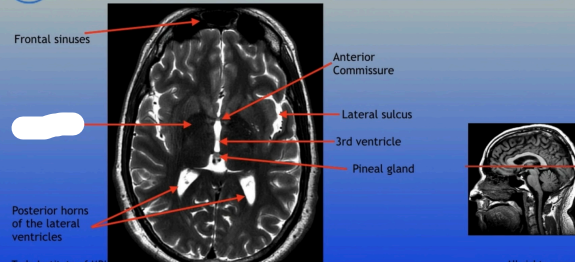

Frontal Sinus

Posterior Horn of Lateral Ventricle

Frontal Sinuses

Posterior Horns of the Lateral Ventricles

Anterior Commissure